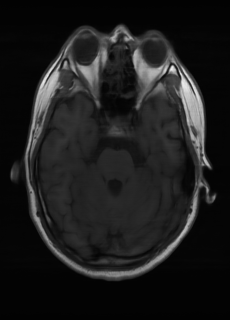

As we observe from the right image in Fig. 2, our BRM, both from MIMO and SISO settings, predicts the performance of dedicated models with a high correlation. We further choose the best three , and perform the last stage of fine-tuning accordingly to (6). A visual evaluation on real data is shown in Fig. 3. For simulated data, please refer to the Supplemental Material section.

Base on the best performing , we perceive that among , , and FLAIR, the results are best when is sampled the most. We suggest that this makes intuitive sense as images provide the best contrast out of the three sequences, which can compensate for the details lost in other images. The same observation can be made on the simulated data, where both and FLAIR show good contrast. When the time setting is changed to non-uniformity, we can see that our search for the best sampling strategy reflects the change. is sampled more as a result of faster acquisition time, while is still sufficiently sampled.

| Sequence | LR | SISO | MIMO | MIMO tuned | GT |

|---|---|---|---|---|---|

(a) 34.38/0.9371

(a) 34.38/0.9371

|

(b) 42.42/0.9883

(b) 42.42/0.9883

|

(c) 44.60/0.9920

(c) 44.60/0.9920

|

(d) 45.50/0.9940

(d) 45.50/0.9940

|

(e) PSNR/SSIM

(e) PSNR/SSIM

|

|

(f) 29.74/0.8903

(f) 29.74/0.8903

|

(g) 36.25/0.9734

(g) 36.25/0.9734

|

(h) 36.42/0.9752

(h) 36.42/0.9752

|

(i) 37.70/0.9832

(i) 37.70/0.9832

|

(j) PSNR/SSIM

(j) PSNR/SSIM

|

|

(k) 39.89/0.9311

(k) 39.89/0.9311

|

(l) 43.94/0.9864

(l) 43.94/0.9864

|

(m) 44.74/0.9883

(m) 44.74/0.9883

|

(n) 45.49/0.9894

(n) 45.49/0.9894

|

(o) PSNR/SSIM

(o) PSNR/SSIM

|